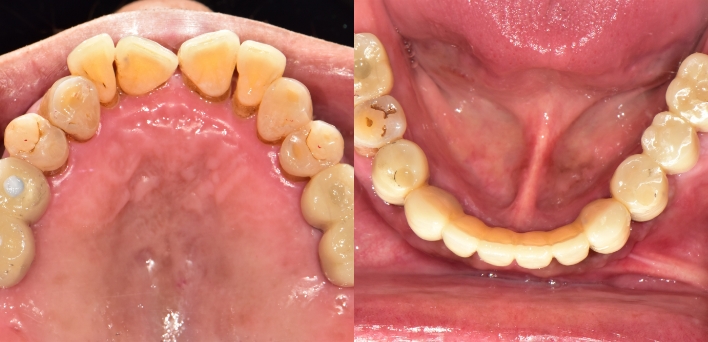

임플란트 : 손 ** 님 (50대)

치아가 있다는게, 아직도 정말 꿈만 같아요.

Before Before

2020.02.30

After After

※ 더서울치과의원은 의료법을 준수하며 위 케이스는 실제 환자의 동의를 얻은 사례로 치료 전, 후가 동일한 환경에서 촬영되었습니다.

환자 케이스에 따라 부작용이 발생할 수 있습니다. 이 부분은 의료진의 충분한 상담과 체크를 통해 예방하고 줄일 수 있습니다.

[임플란트 부작용] 수술 후 관리가 소홀할 경우 출혈, 주위염 등의 부작용이 발생할 수 있어 구강 위생을 철저히 유지하고, 정기적인 검진을 통해 상태를 점검하는 것이 중요합니다.

환자 특징

환자 특징01무치악 상태

환자 특징02수년간 무치악으로 지내심

임플란트가 불가능할것이라

생각하고 내원

위, 아래 6개씩 식립

디지털 풀아치 임플란트